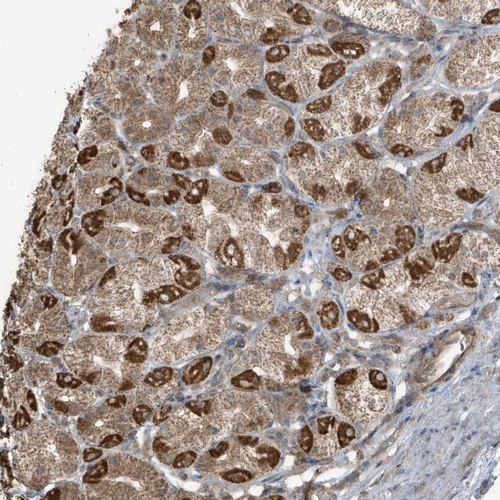

Immunohistochemical staining of human stomach shows strong cytoplasmic positivity in parietal cells.